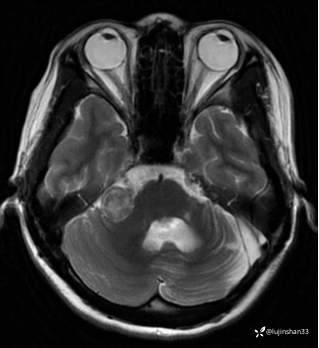

第一次术前颞骨CT及MRI:

第二次术前CT及MRI